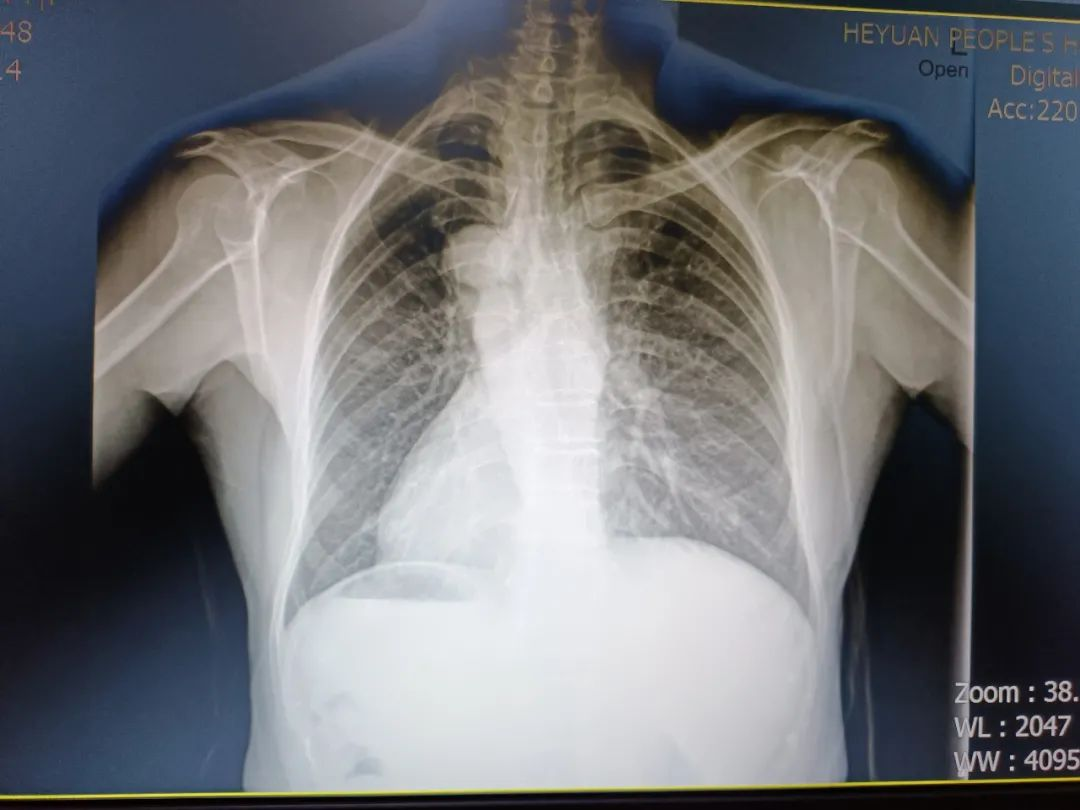

胸片提示心脏完全反位